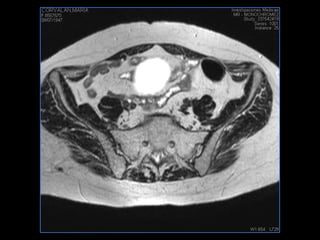

PROTOCOLO pelvis SAG T2, Y FAT SAT (FINOS) AXIAL T1  AX FAT SAT CON   GADOLINIO :  AX T1 Y COR T1 SAT: NO  FASE: RL THK: 3MM  COIL:  GAP: (FACTOR 1.4) 1MM FOV: 40 CM NEX:2 SINCRONIZACION RESPIRATORIA EN 3 O 4 CICLOS ALE

resonancia de abdomen